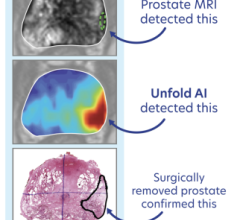

June 15, 2022 — Current guidelines used to plan salvage radiation treatments in patients with local recurrence of prostate cancer should be updated to take into consideration information derived from novel imaging modalities, such as PSMA PET, according to research presented at the Society of Nuclear Medicine and Molecular Imaging 2022 Annual Meeting. The study showed that PSMA PET was effective in identifying recurrences that fell partially or fully outside of the clinical target volume as determined by current guidelines. This suggests that PSMA PET can be an invaluable tool for therapy planning.

After a biochemical recurrence of prostate cancer, salvage radiation therapy can be a curative approach. This therapy conducted following contouring guidelines based on expert consensus, such as the Radiation Therapy Oncology Group (RTOG) guidelines. In today’s era of precision medicine, study authors sought to determine if PSMA PET imaging could provide more detailed data on patterns of recurrence to inform therapy planning.

Prostate cancer patients who experienced biochemical recurrence after radical prostatectomy were included in the analysis if their PSMA PET/CT imaging showed recurrence in the prostate bed. To analyze the patterns of recurrence, two nuclear medicine physicians documented the areas of recurrence on the PSMA PET/CT, and four radiation oncologists (masked to the PSMA PET/CT findings) delineated the clinical target volume using RTOG guidelines on the CT images of the PET/CT. PSMA recurrence locations were then compared to the RTOG-based clinical target volumes.

PSMA recurrences were fully covered by the clinical target volumes in 54 percent of the patients. In 34 percent of the patients, PSMA recurrence was only partly covered, and in 13 percent of patients the PSMA recurrence was located fully outside of the clinical target volume.

“This study has the potential to redefine prostate bed contouring guidelines to improve the therapeutic ratio for patients receiving postoperative radiotherapy,” said Ida Sonni, MD, project scientist in the Department of Radiology at the University of California, Los Angeles. “Nuclear medicine and molecular imaging advances, such as PSMA PET, have the ability to guide individualized, tailored treatments that will ultimately benefit all our patients.”